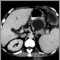

A pancreatic pseudocyst is a collection of tissue, fluid, debris, pancreatic enzymes, and blood in the abdomen. It can develop after acute pancreatitis.

Pancreatic pseudocysts usually develop after an episode of severe, acute pancreatitis. They often happen when the pancreatic ducts are disrupted by inflammation that occurs during pancreatitis. Risk factors for a pancreatic pseudocyst are acute pancreatitis, abdominal trauma, and chronic pancreatitis.